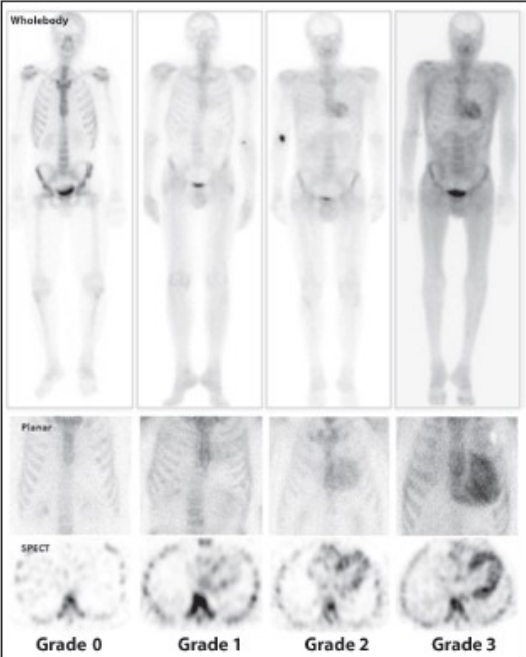

Un’applicazione clinica specifica è la diagnosi di amiloidosi cardiaca transtiretina-correlata (ATTR). I difosfonati (HDP o DPD) si legano ai depositi di amiloide nel miocardio. La gravità viene valutata tramite lo score di Perugini.

Grado score di Perugini

Descrizione della captazione miocardica

Grado 0

Assenza di captazione cardiaca

Grado 1

Captazione cardiaca inferiore a quella delle coste

Grado 2

Captazione cardiaca uguale a quella delle coste

Grado 3

Captazione cardiaca superiore a quella delle coste (segnale osseo attenuato)

L’analisi semiquantitativa tramite il rapporto Cuore/Contro-Laterale (H/CL) con un cut-off di 1.37-1.40 supporta ulteriormente la diagnosi.

Perugini Score visivo rispettivamente sulle immagini total body, sulle immagini statiche planari e sulle immagini tomografiche assiali.

Il Perugini Score è un sistema di valutazione visiva semiquantitativa utilizzato in diagnostica radiometabolica (con traccianti osteotropi come 99mTc-DPD, HMDP o PYP) per classificare l’entità della captazione miocardica. È il gold standard non invasivo per la diagnosi di amiloidosi cardiaca da transtiretina (ATTR).

Le immagini planari (Total Body e statiche): offrono una panoramica generale e permettono il confronto visivo diretto tra l’area cardiaca e lo scheletro.

Le immagini tomografiche assiali (SPECT o SPECT/TC): sono dirimenti per confermare che la captazione risieda effettivamente nel miocardio (soprattutto nel miocardio ventricolare), escludendo falsi positivi dovuti a residui di tracciante nel blood-pool (pool ematico intracavitario), sovrapposizioni costali o patologie pleuro-polmonari.